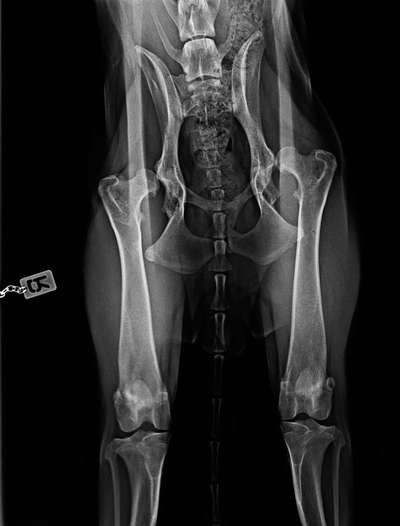

Guten Morgen 🤗 ich wollte euch mal ein paar Neuigkeiten mitteilen und erst einmal:Keine Sorge,dass ist nicht die Hüfte von Puma,zum Glück,ihre ist in Ordnung.

Das ist die Hüfte von einer von Pumas jüngeren Schwestern,die ist 10 Monate alt und hat dieses Problem schon von Geburt an.Ist natürlich deswegen auch etwas anders gelaufen,die jetzigen Besitzer haben die mit 6 Monaten bekommen,aber die Züchter haben nichts gesagt.Ein Anwalt ist eingeschaltet und hoffentlich dürfen die nie wieder züchten.Ich habe da einiges Neues erfahren,was ich vorher noch nicht gewusst habe und meine Meinung ist sogar schon im unteren Teil des negativen Bereiches,wobei ich vorher dachte,die könnte nicht weiter runtergehen.